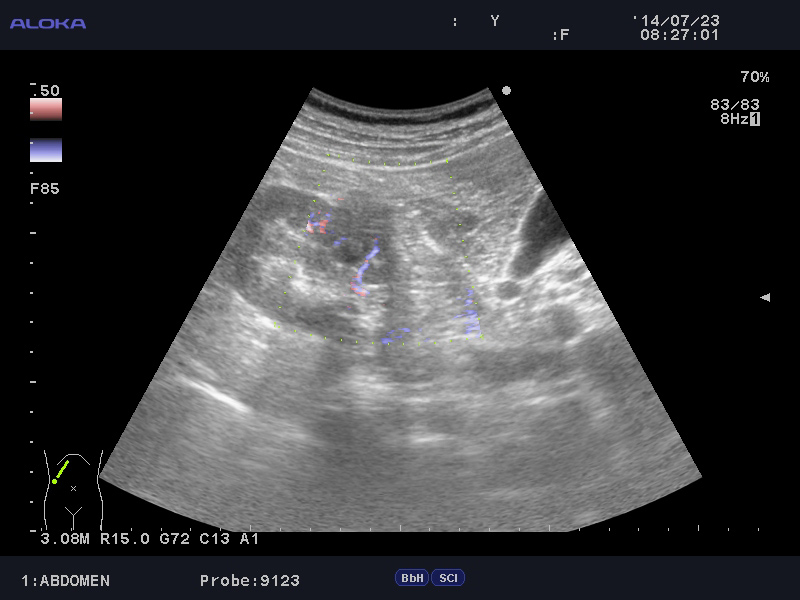

Образование в правой почке

Мужчина средних лет.Жалоб не предъявляет.

С его слов, 10 лет назад в правой почке находили кисту.

Aloka alpha 6

гипоэхогенное образование в среднем сегменте, деформирующее контур почки...наверное рак

Кровотока ни грамма- Киста

Динамики нет, на последнем видео четко видна киста при включенной 2й гармонике